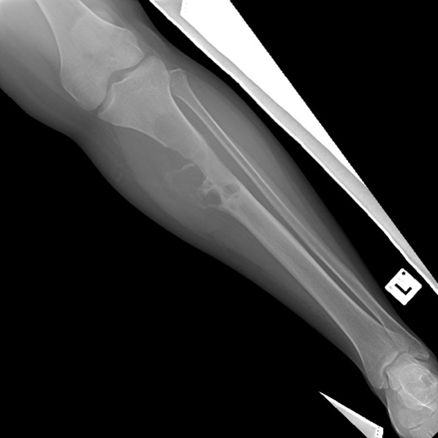

Endoprosthetic replacement. An example of a wide local resection of a patient who had an osteosarcoma of her proximal tibia. The initial X-rays show the pervasive lytic lesion of the proximal tibial diaphysis and metaphysis. The subsequent X-rays show an endoprosthetic replacement called a proximal tibial replacement. The knee has been replaced with a hinge-type knee replacement and the bone and tumour of the proximal tibia has been replaced by a modular metal prosthesis with a stem cemented into the distal femur and the proximal tibia.